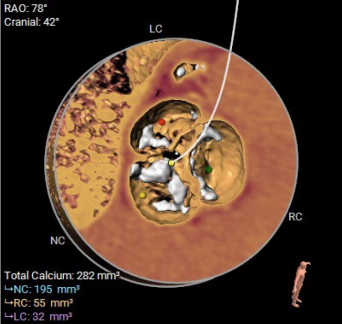

▲术前CT评估

团队没有贸然手术,而是先对庄爷爷进行了全面细致的术前评估:通过 CT 精准测量主动脉根部、冠脉高度、入路血管等关键数据,结合超声心动图评估心脏功能,最终确定为他实施 TAVR 微创手术。